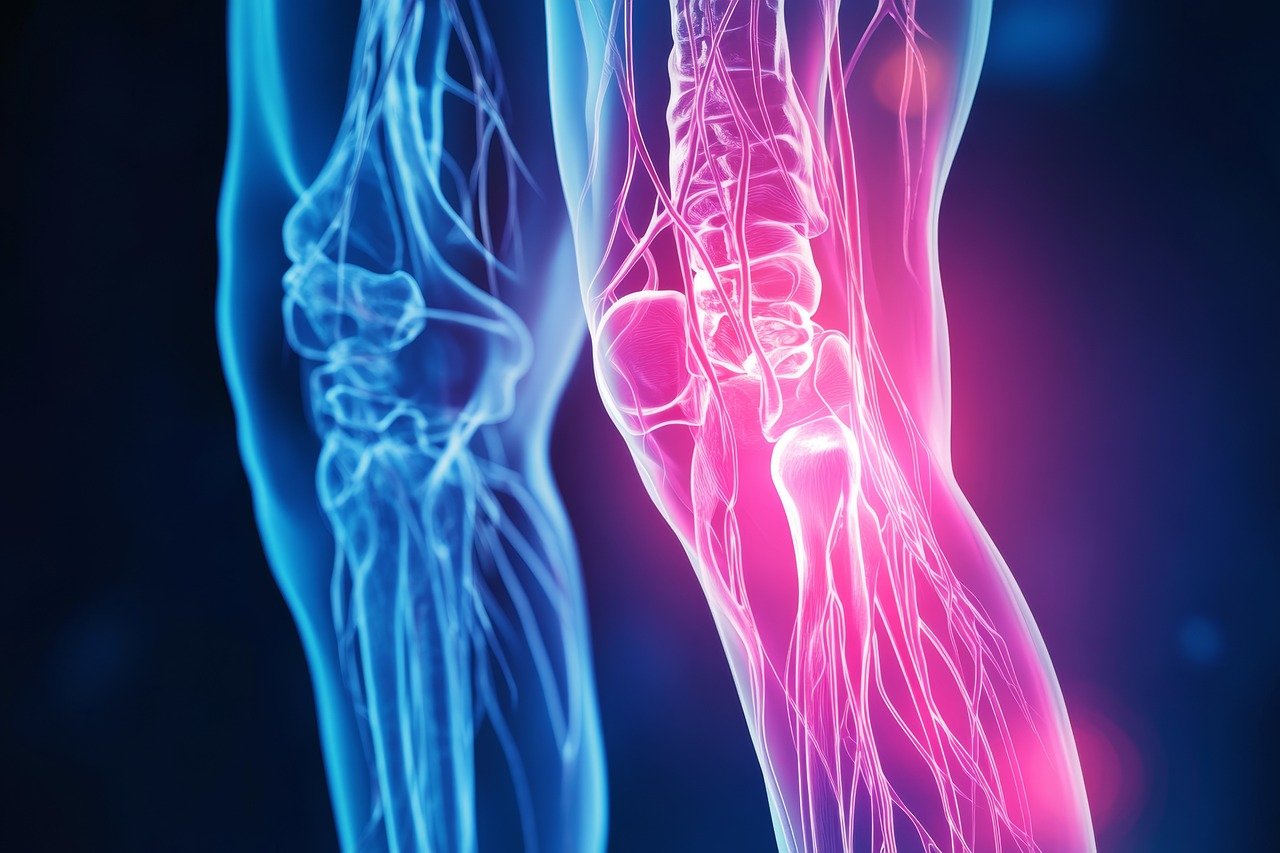

퇴행성 관절염은 관절의 연골이 점진적으로 손상되고 마모되는 만성 질환으로, 흔히 나이가 들면서 발생하는 질환 중 하나입니다.

이 질환은 관절의 움직임을 제한하고 통증을 유발해 일상생활에 불편을 초래합니다.

하지만 연골이 손상되거나 얇아지면 뼈끼리 맞닿아 마찰이 발생하게 되고, 이는 염증과 통증을 유발합니다.

1. 관절통증

관절을 움직일 때 통증이 발생하거나, 휴식 후에도 지속적인 통증을 느낌